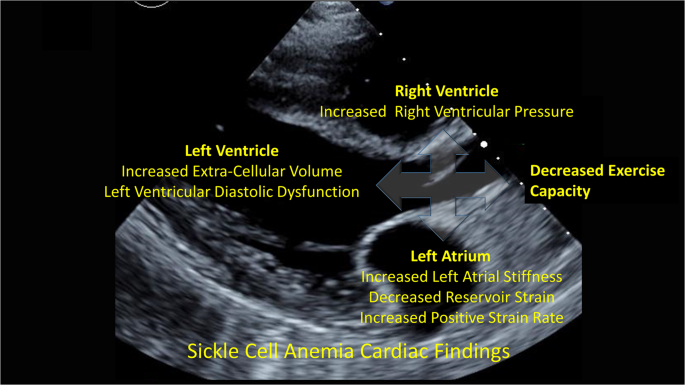

In summary, we have shown that LA stiffness is associated with elevated TRV and poor exercise capacity in children and adults with SCA. LA dysfunction is also associated with ventricular ECV, suggesting that LV diffuse interstitial myocardial fibrosis may lead to impaired LA function and subsequently to elevated pulmonary pressures (Fig. 6). The therapeutic targeting of both atrial stiffness and ventricular fibrosis to potentially ameliorate cardiac complications and improve outcomes in SCA are needed.